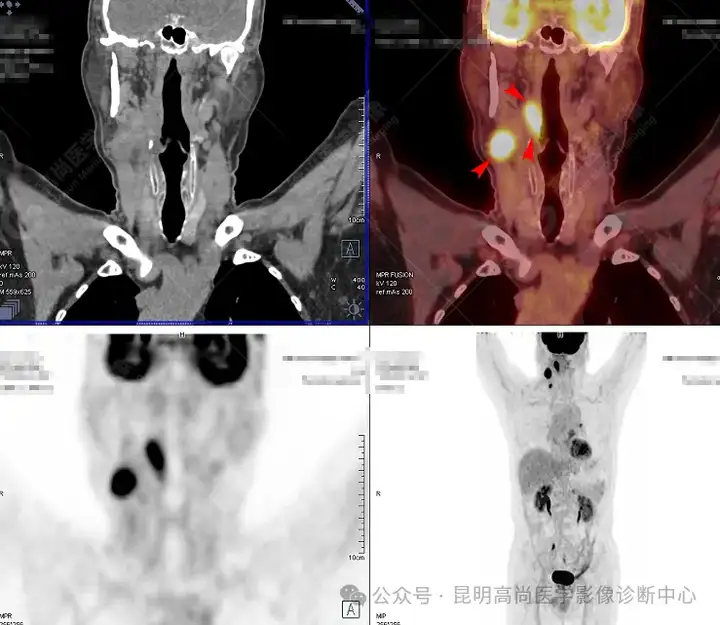

PET全身MIP图

大范围冠状位可见口咽后侧壁病变及颈部转移淋巴结

口咽右侧壁及右侧颈部多发高代谢灶

延时显像口咽右侧壁及右侧颈部病变糖代谢持续增高

1、口咽部右侧壁及部分前壁增厚并右侧腭扁桃体区肿块影形成,糖代谢持续明显增高,考虑恶性病变,建议对口咽右侧壁活检;

2、 双颈颈Ⅱ、Ⅲ、Ⅳ、Ⅴ区、左肺门(10组)及纵隔(4、5组)多发淋巴结显示,其中右颈Ⅱ、Ⅳ区、左肺门(10组)及纵隔5组淋巴结明显增大并糖代谢持续不同程度增高,符合转移淋巴结表现,余淋巴结反应性增生可能,建议随诊。

通过 PET/CT影像,肺、食管等器官无明确实体性肿瘤,诊断口咽来源恶性肿瘤可能性大(回访明确为口咽部恶性肿瘤,已经开始相应治疗)。